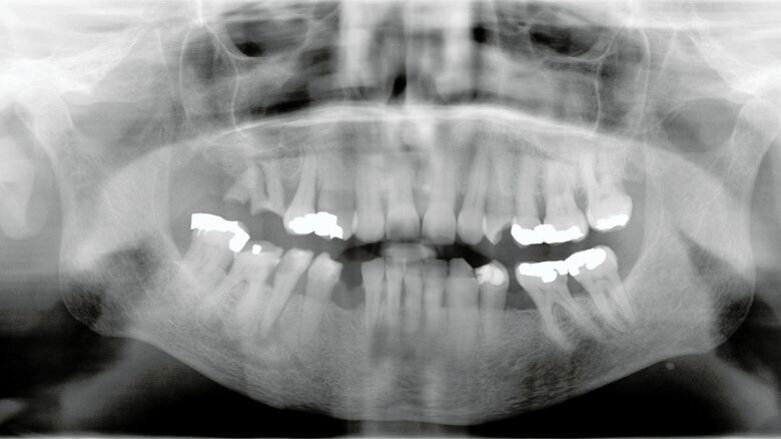

Ze had koorts (39,8 C0), een beperkte mondopening en de solo paste niet meer. De OPG wees op een forse parodontitis apicalis uitgaande van de 45. De injectie met QuickSleeper tussen 46 en 47 ging nog net ondanks de beperkte mondopening. De patiënt bleef heel rustig en heeft de injectie niet gevoeld. Na spoelen met water werd meteen op meerdere plaatsen naast het element gesondeerd met een endo-sonde. Met de tang werd het element verwijderd. Tot Hellebrekers’ verbazing leidde de anesthesie en de extractie tot nul reactie bij de patiënt Ze had absoluut niets gevoeld. Hellebrekers: “Onwerkelijk dat dit kan. Bij conventionele behandeling is met name de anesthesie heel pijnlijk. En bijna ook altijd de extractie.”